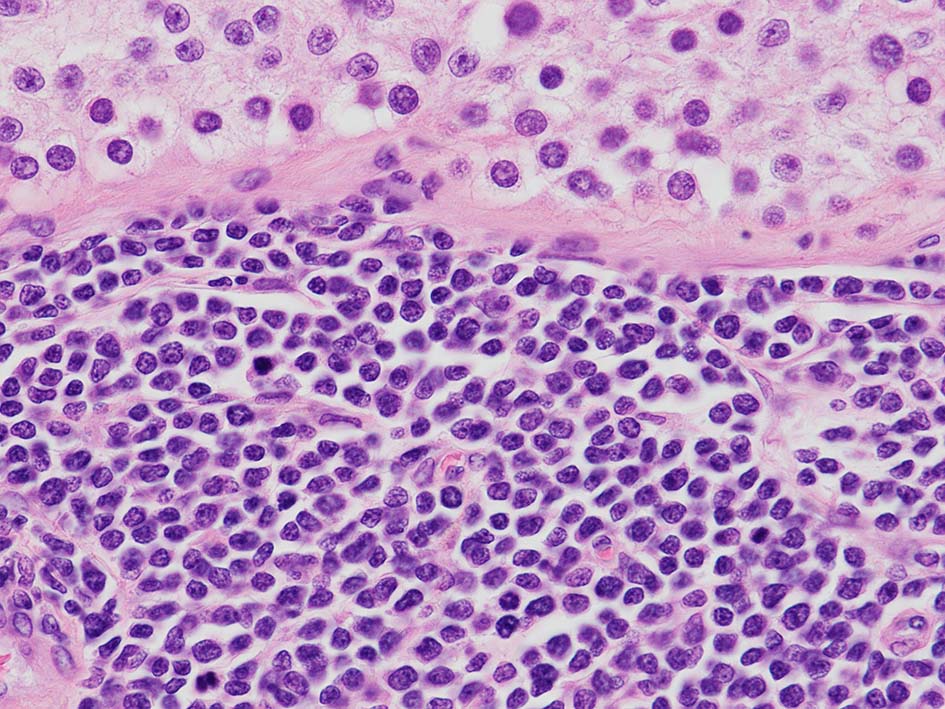

loupe像Aの領域: 精細管をスペアするように, 小型リンパ球優位, 一部中型のlymphoid cellsがシート状密に浸潤増殖する. tubulesのほとんどにはlymphoid cellsが浸潤していないが, LELに似たようなlympho-tubular lesionが少数認められた. x400高倍率では, 増殖細胞は, 粗く, 凝集したクロマチンをもつ類円形, non-cleavedな核をもつ細胞質の乏しいlymphoid cellsである. 核小体か凝集したクロマチンかわかりにくい.

白膜には密に腫瘍性リンパ球が浸潤増殖し, 肥厚, 一部は上図loupe像のように, 腫瘤を形成している. 浸潤リンパ球は精巣実質内よりも, やや大きく, 多稜形, くびれのある核をもち, クロマチンは淡明で核小体が明瞭になってきている.